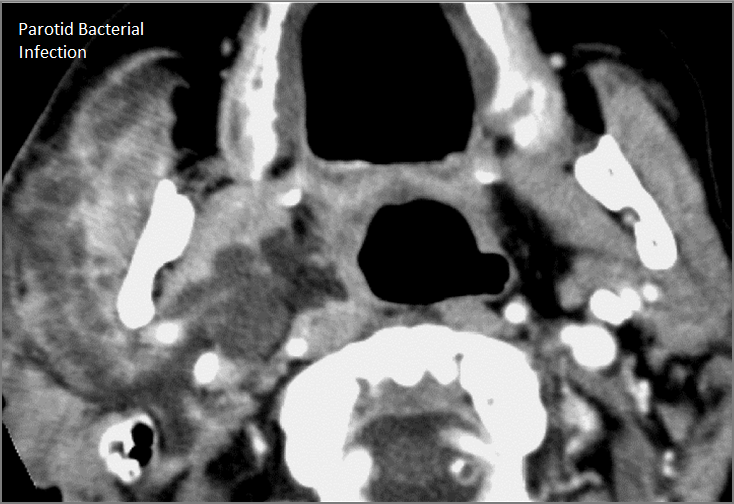

Major Salivary Glands

There is significant abnormality of the parotid, submandibular or sublingual glands that would be an alternate explanation for the patient’s symptoms. [Yes/No]